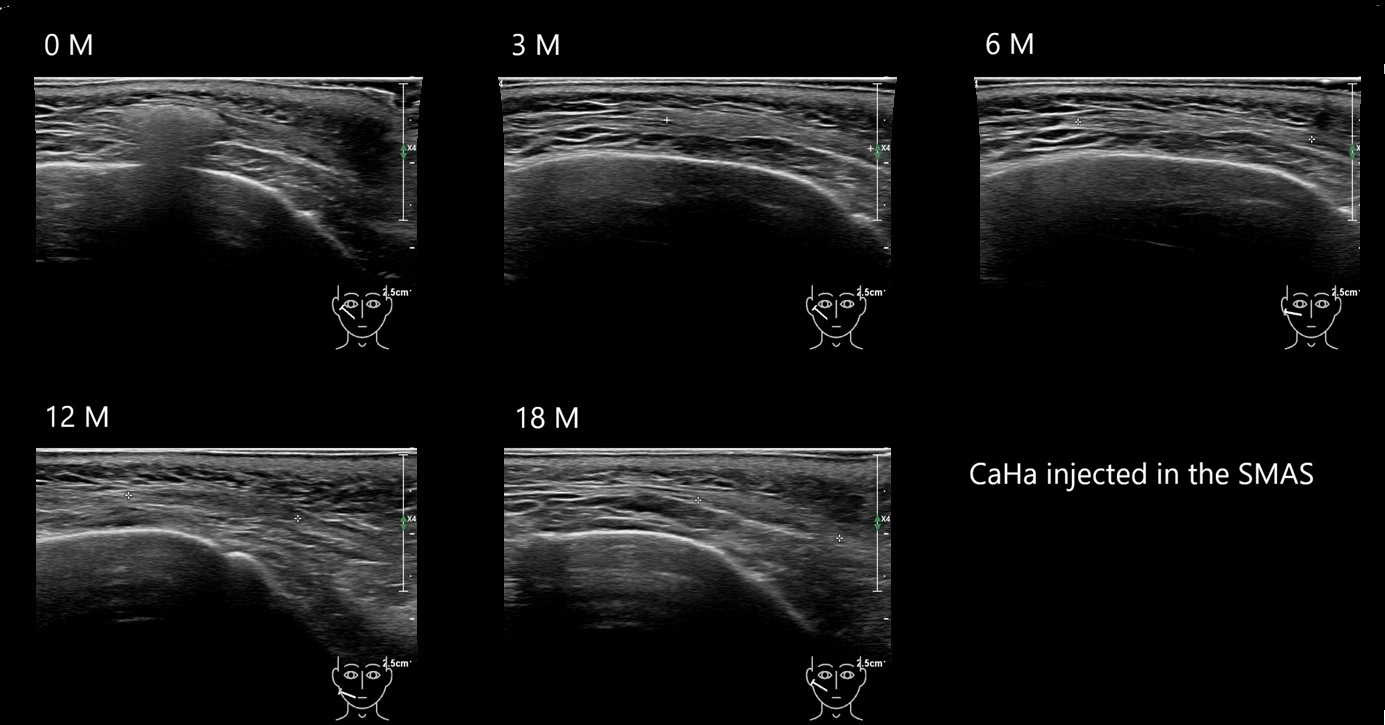

Draw in the image on the right where the fillers are located. To check if your answer is correct, please click on the secondary image.

Draw in the second image below where the fillers are located. To check if your answer is correct, swipe the first image to the right.